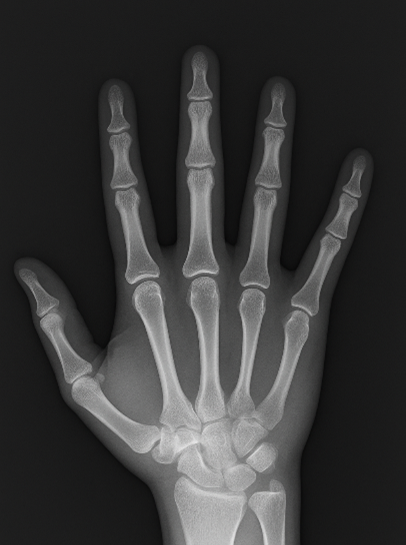

- 撮影

撮影部位に応じて放射線技師が姿勢を指示します。

その際、体に触れたり動かしたりすることがあります。

撮影後、画像を確認して検査終了となります。